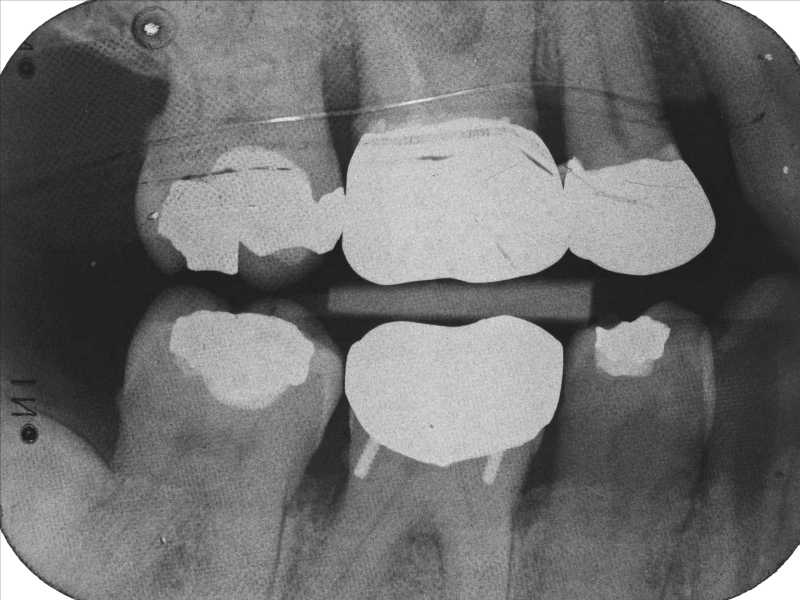

Technical Errors in Intra Oral Radiographs Obtained in Endodontic Dental Errors Brushing too hard, using floss picks and other mistakes that put the. Poor margin detail will likely lead to open. however, if the dentist is unable to identify the cause of the error in the original impression, the mistake may very well be. technique errors can occur if any of these steps are completed improperly. most often,. Dental Errors.